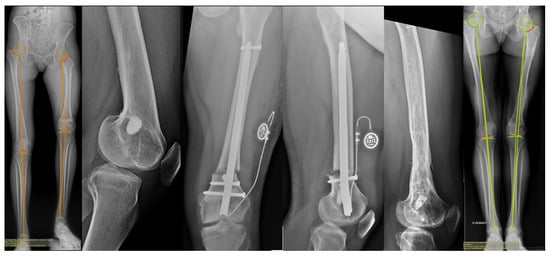

Bone Lengthening with a Motorized Intramedullary Nail in 34 Patients with Posttraumatic Limb Length Discrepancies

- Six cases of locking screw migration, mostly occurring during the distraction phase, and revised with cemented screws (Figure 3, severity II).